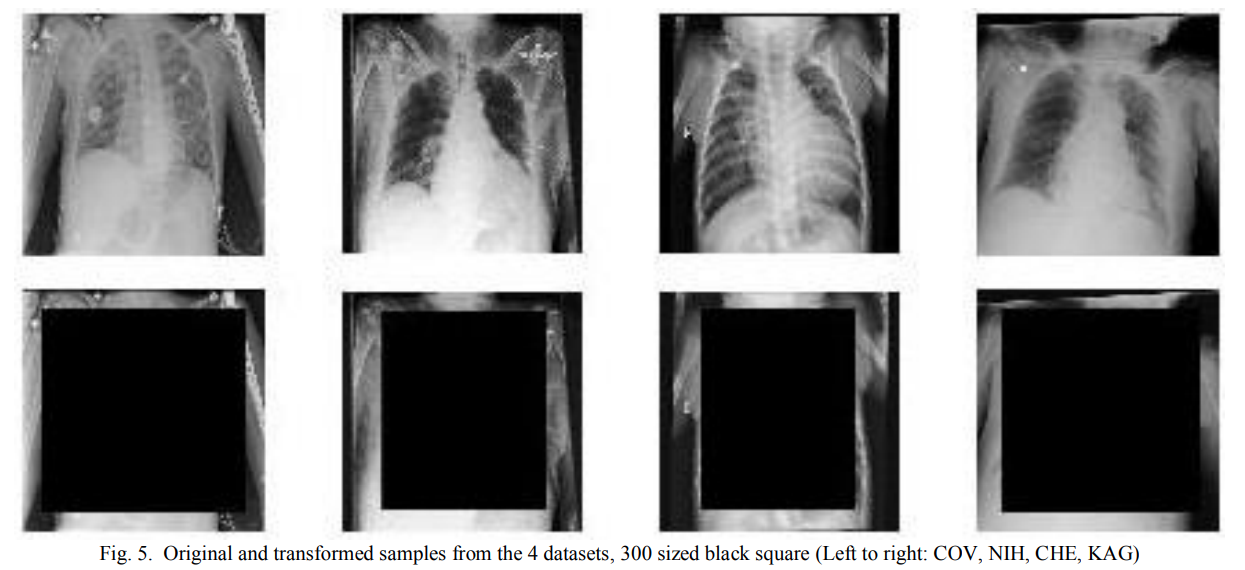

Early in the COVID-19 pandemic, many papers claimed that deep learning models could diagnose COVID-19 from chest radiographs. A later review found that none of the surveyed models were of potential clinical use due to methodological flaws and underlying biases.11

A major source of failure was the use of Frankenstein datasets. Researchers would combine an emerging COVID-19 X-ray dataset with one or more existing X-ray datasets (for example, datasets built for viral vs bacterial pneumonia). In many of these combinations, the “COVID” images and the “non-COVID” images came from different hospitals, different machines, different preprocessing pipelines, and sometimes different patient populations. The images were so distinctive to their source dataset that a model could learn to recognize the dataset itself, rather than the disease.

In some “COVID vs non-COVID” constructions, the non-COVID examples were taken from pediatric chest X-ray datasets. Models that appeared to learn COVID vs non-COVID pneumonia ended up with zero clinical value, because they were actually learning artifacts correlated with the label in the training data, for example, child vs adult body structure. In fact, researchers showed that similar performance could be achieved even when most of the lung region was masked out, indicating that the model was not learning the intended clinical signal.12

This example highlights the important of (1) looking at the data, and having enough domain expertise to interpret it - for example, to distinguish between adults and children in X-rays! (2) understanding the data lineage - including how it was collected and who it was collected from (3) sanity-checking results with domain experts - in this case, radiologists understood that differences between COVID and non-COVID pneumonia were not usually obvious in radiography, and could have flagged this as an unreasonable result.